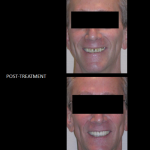

Full Mouth Reconstruction - restoring missing tooth structure (from years of tooth wear) using high strength crowns gave this man his smile back, improved his chewing, and helped protect his teeth from future damage.

Full Mouth Reconstruction - restoring missing tooth structure (from years of tooth wear) using high strength crowns gave this man his smile back, improved his chewing, and helped protect his teeth from future damage.

Full Mouth Reconstruction - restoring missing tooth structure (from years of tooth wear) using high strength crowns gave this man his smile back, improved his chewing, and helped protect his teeth from future damage.

Full Mouth Reconstruction - restoring missing tooth structure (from years of tooth wear) using high strength crowns gave this man his smile back, improved his chewing, and helped protect his teeth from future damage.